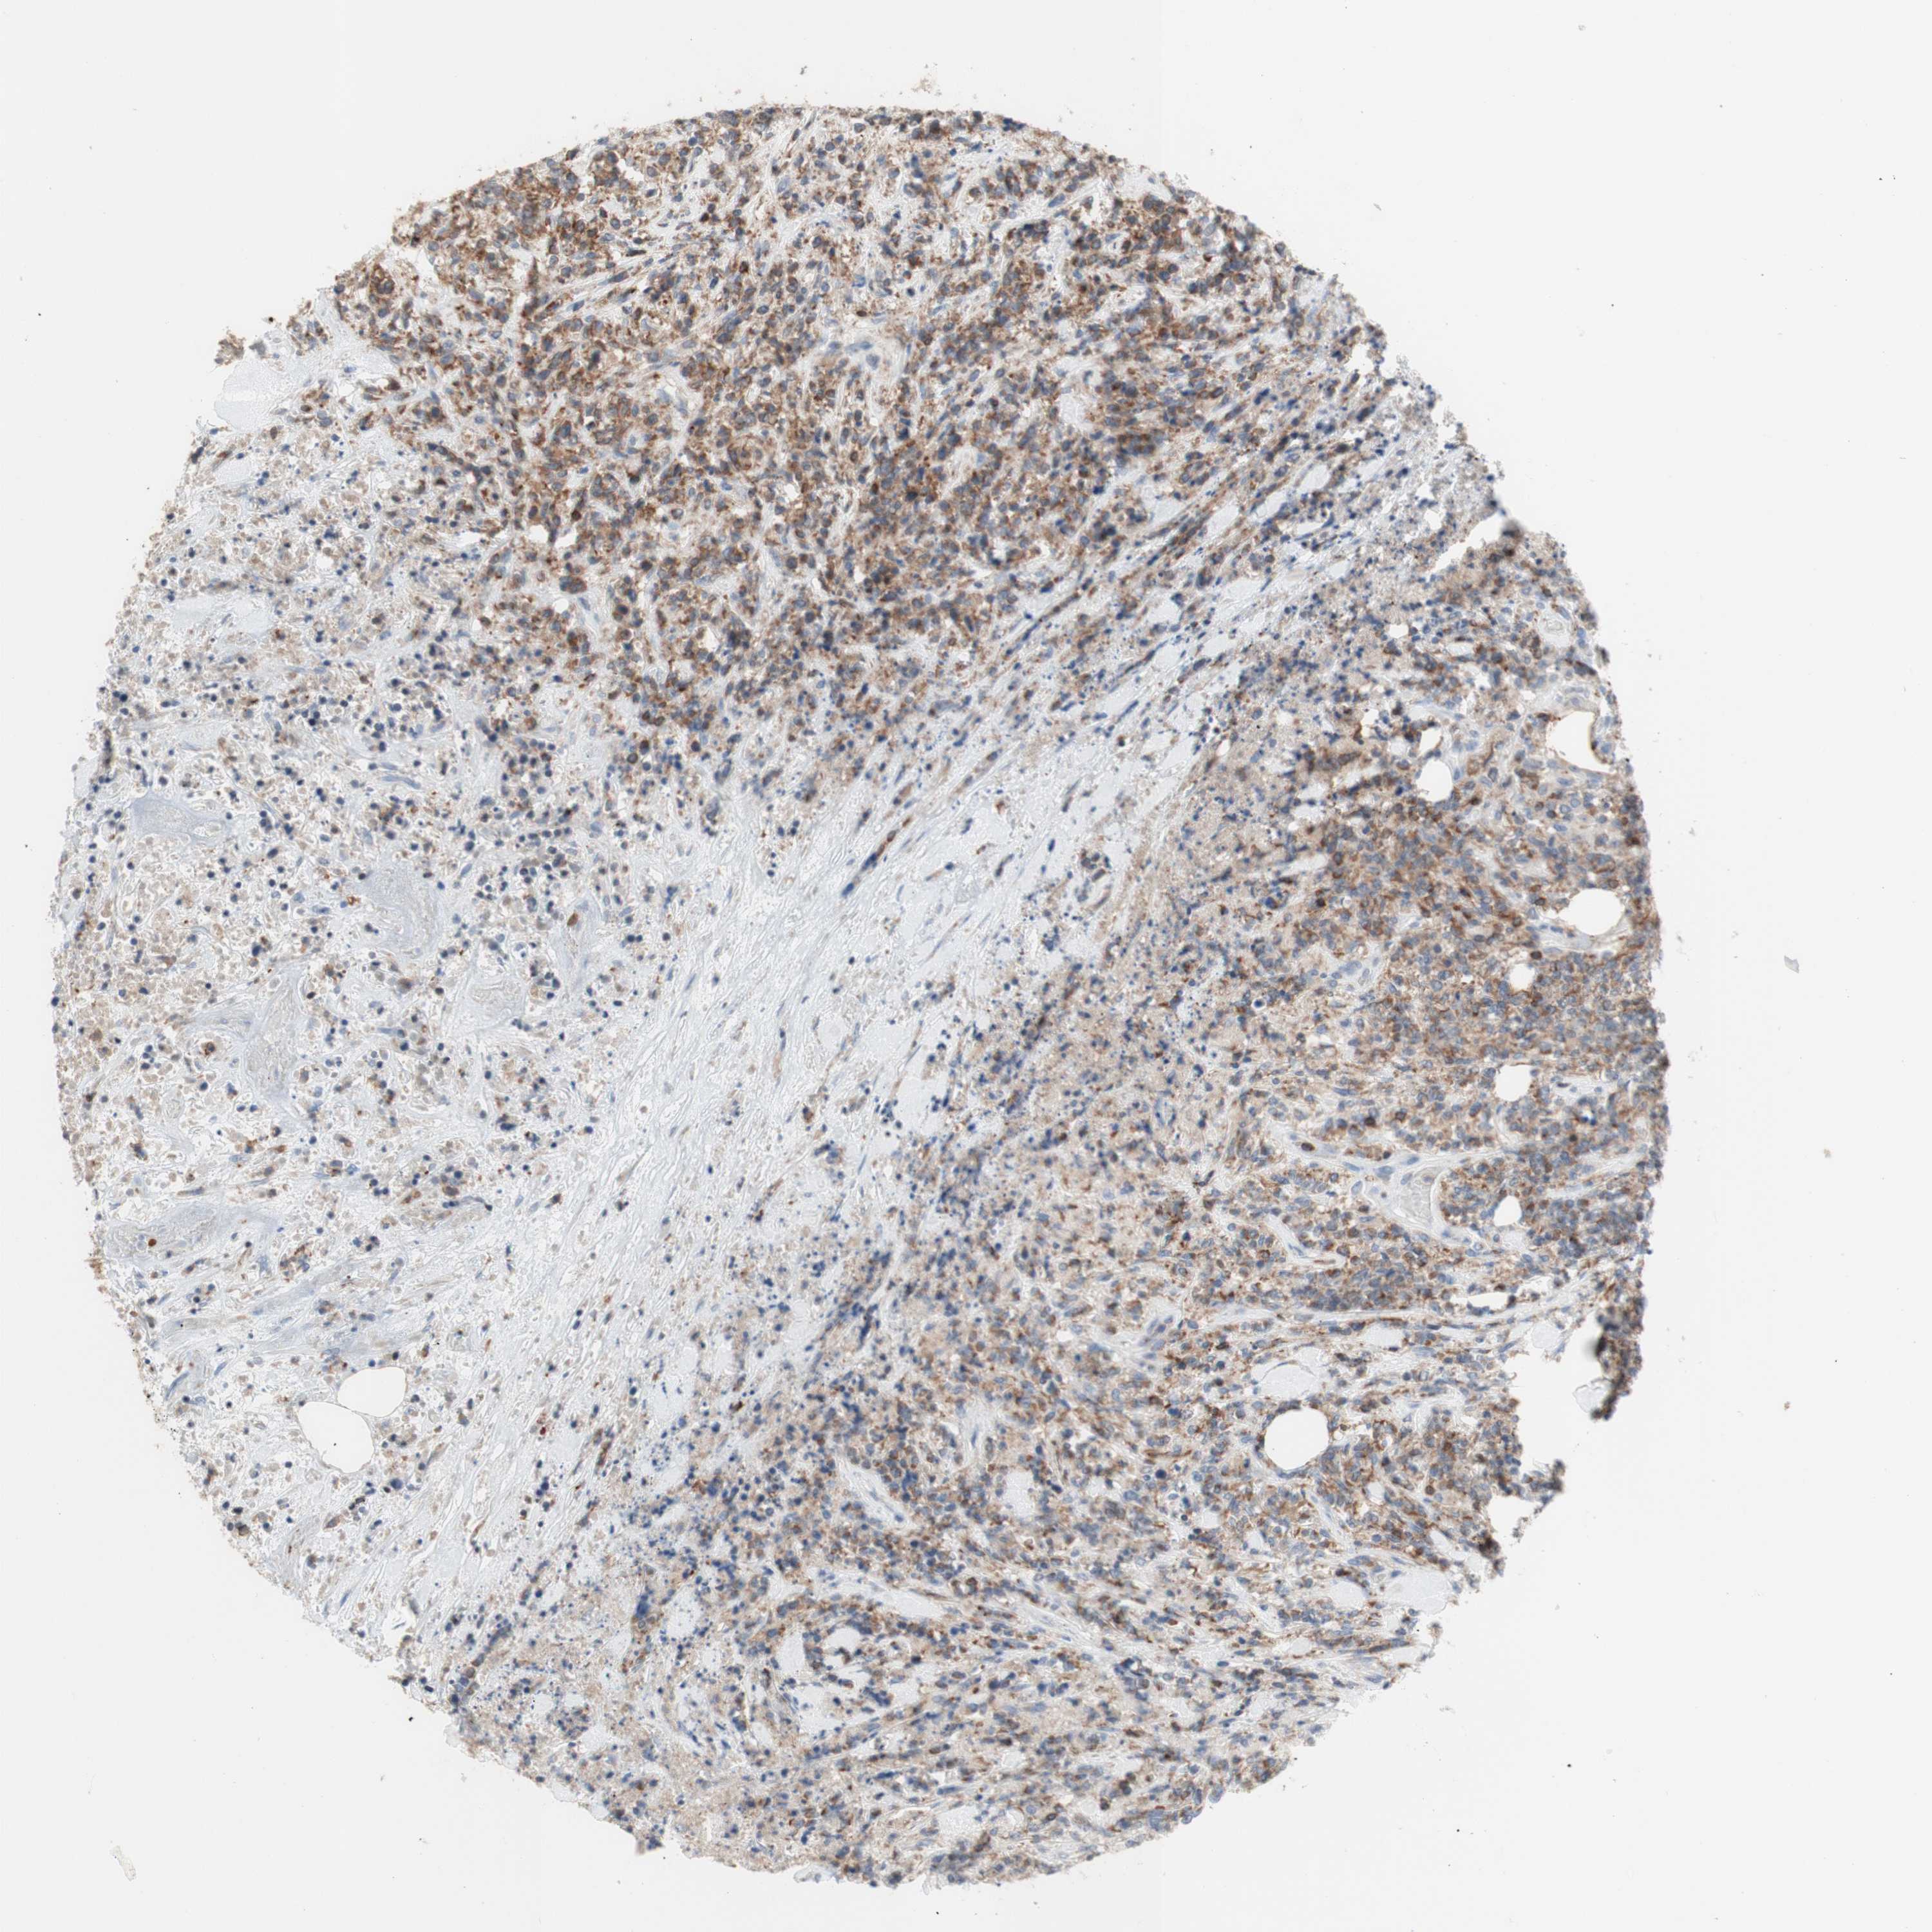

CANCER LYMPHOMA Show tissue menu

LYMPHOMA - Protein expressioni

A mouse-over function shows sample information and annotation data. Click on an image to view it in a full screen mode. Samples can be filtered based on level of antibody staining by selecting one or several of the following categories: high, medium, low and not detected. The assay and annotation is described here.

Antibody stainingi

Antibody staining in the annotated cell types in the current human tissue is reported as not detected, low, medium, or high, based on conventional immunohistochemistry profiling in selected tissues. This score is based on the combination of the staining intensity and fraction of stained cells.

Each image is clickable and will lead to virtual microscopy that enables deeper exploration of all samples and also displays staining intensity scores, fraction scores and subcellular localization as well as patient and tissue information for each sample.

Antibody HPA011039

Staining

High

Medium

Low

Not detected

Intensity

Strong

Moderate

Weak

Negative

Quantity

>75%

75%-25%

<25%

None

Location

Nuclear

Cytoplasmic/membranous

Cytoplasmic/membranous,nuclear

Hodgkin's disease, NOS

Malignant lymphoma, non-Hodgkin's type, Low grade

Malignant lymphoma, non-Hodgkin's type, High grade